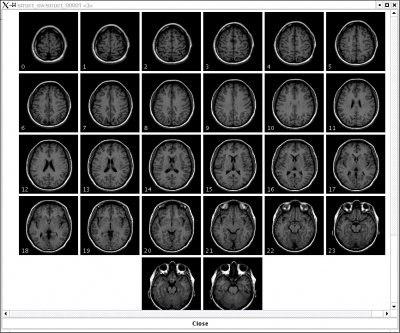

part of Player Photograph

Quite possibly my most revealing photo.